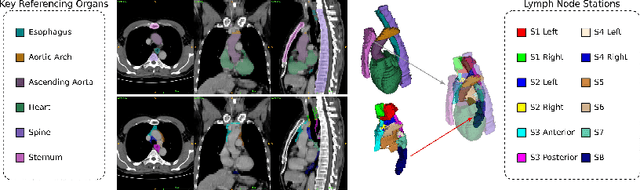

Abstract:Lymph node station (LNS) delineation from computed tomography (CT) scans is an indispensable step in radiation oncology workflow. High inter-user variabilities across oncologists and prohibitive laboring costs motivated the automated approach. Previous works exploit anatomical priors to infer LNS based on predefined ad-hoc margins. However, without voxel-level supervision, the performance is severely limited. LNS is highly context-dependent - LNS boundaries are constrained by anatomical organs - we formulate it as a deep spatial and contextual parsing problem via encoded anatomical organs. This permits the deep network to better learn from both CT appearance and organ context. We develop a stratified referencing organ segmentation protocol that divides the organs into anchor and non-anchor categories and uses the former's predictions to guide the later segmentation. We further develop an auto-search module to identify the key organs that opt for the optimal LNS parsing performance. Extensive four-fold cross-validation experiments on a dataset of 98 esophageal cancer patients (with the most comprehensive set of 12 LNSs + 22 organs in thoracic region to date) are conducted. Our LNS parsing model produces significant performance improvements, with an average Dice score of 81.1% +/- 6.1%, which is 5.0% and 19.2% higher over the pure CT-based deep model and the previous representative approach, respectively.